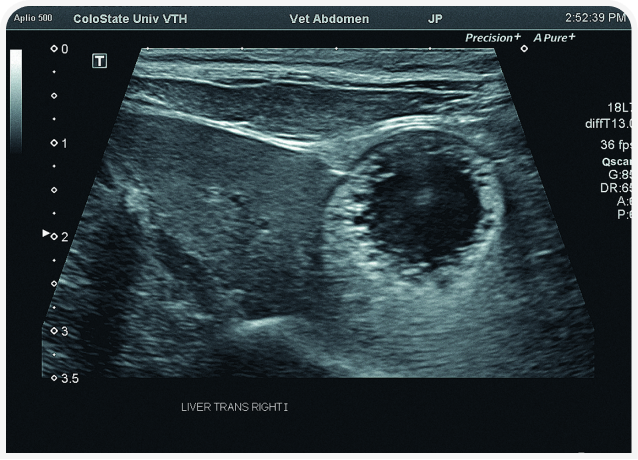

Решающее значение для диагностики и лечения в этом случае будет иметь ультразвуковое исследование органов брюшной полости (Рисунок 6). Диагностику триадита у кошек облегчают визуализация поджелудочной железы и определение толщины/архитектоники стенки кишечника; изменения в паренхиме печени по-прежнему остаются неспецифичными, но изменения в желчном пузыре, скорее всего, помогут установить диагноз. При нейтрофильном холангите у кошки результаты визуализации желчных путей могут оказаться нормальными, но во многих случаях стенка желчного пузыря будет утолщенной и неровной, даже зубчатой (Рисунок 7) (22). Возможны осадок (Рисунок 8) или наличие камней в желчном пузыре, поэтому желчевыводящие пути важно просмотреть до двенадцатиперстной кишки, чтобы исключить внепеченочную окклюзию желчных протоков. Во многих случаях общий желчный проток оказывается перекрыт. Возможен асцит, и в этом случае оправдано проведение аспирации и анализа состава жидкости.

Аспирация содержимого желчного пузыря (чрескожный холецистоцентез под контролем ультразвукового исследования) для цитологического и культурального исследования чаще всего позволяет поставить диагноз и подобрать лечение (Рисунок 9) (23). Если желчный пузырь при визуализации выглядит патологически (например, толщина стенки >1 мм, контур стенки неровный или зубчатый или выраженное гиперэхогенное содержимое (осадок; Рисунок 10), результаты цитологического исследования и бактериального посева, скорее всего, также будут отклоняться от нормы (22,24). Обратите внимание, что при аспирации существует риск разрыва стенки желчного пузыря и/или утечки содержимого с развитием желчного перитонита, но под контролем опытного специалиста УЗИ и при спокойном поведении/седации пациента проблемы возникают редко. Тем не менее если стенка желчного пузыря выглядит эмфизематозной, риск значительно возрастает и вместо аспирации следует рассмотреть возможность хирургического удаления или пробное лечение.